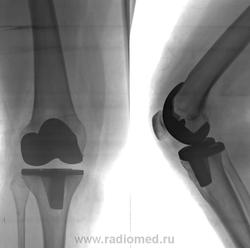

Пол пациента: Мужской пол Тип патологии: Другое Область исследования: Скелетно-мышечная система Методы исследования: Rg Состояние после эндопротезирования. https://radiomed.ru/sites/default/files/styles/case_slider_image/public/user/12/2.201408110109.jpg?itok=DL_OUayU ID:41107 Сб, 23/08/2014 - 22:23 #1 Dima Не на сайте Был на сайте: 7 лет 2 месяцев назад Зарегистрирован: 05.08.2012 - 17:39 Публикации: 2467 Что то не так? Терпимость - это когда прощают чужие ошибки; такт - когда не замечают их. (Артур Шницлер) Сб, 23/08/2014 - 23:32 #2 Nobody Не на сайте Был на сайте: 11 лет 1 месяц назад Зарегистрирован: 15.03.2014 - 20:29 Публикации: 2013 Dima wrote: Что то не так? Нет. Думаю, это пример качественной работы травматологов... Ну, слегка асимметрична суставная щель, но она чутка несимметрична и в норме, поверьте. А лучше проверьте за мной.;)) "Лишь утратив всё до конца, мы обретаем свободу." F.C. Вс, 24/08/2014 - 00:13 #3 Евгений Второй Не на сайте Был на сайте: 1 день 10 часов назад Зарегистрирован: 13.09.2011 - 22:00 Публикации: 1772 А рентгеннегативное вместо хряща что там? Фторопласт? Мениск мой порван конкретно, может тоже придётся что-то протезировать...

А рентгеннегативное вместо хряща что там? Фторопласт? Мениск мой порван конкретно, может тоже придётся что-то протезировать...